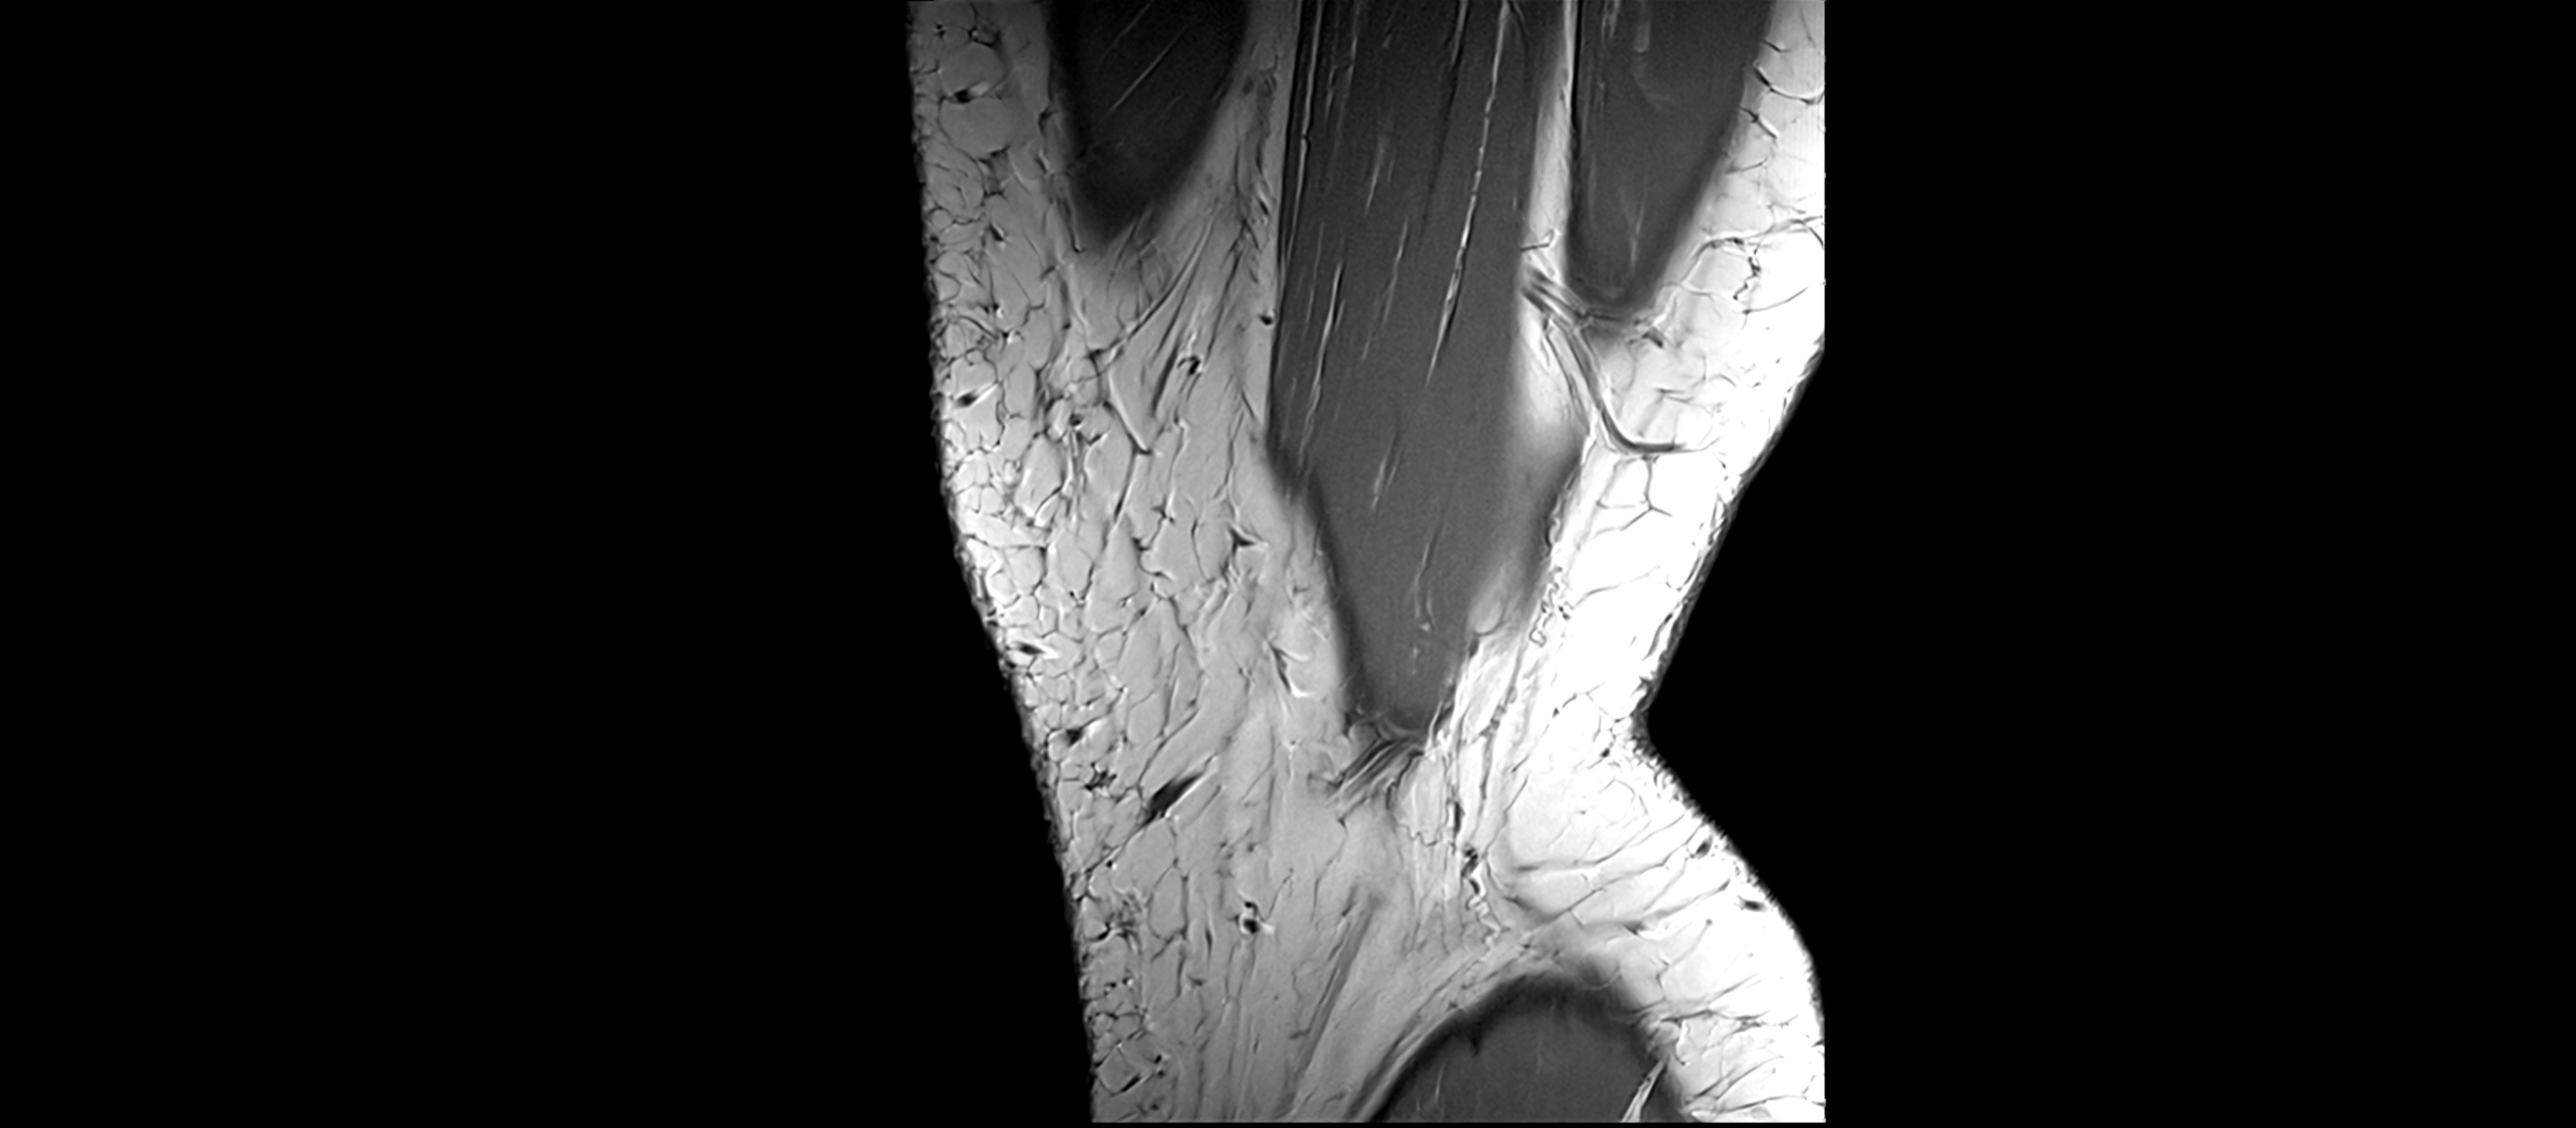

MRI images

image